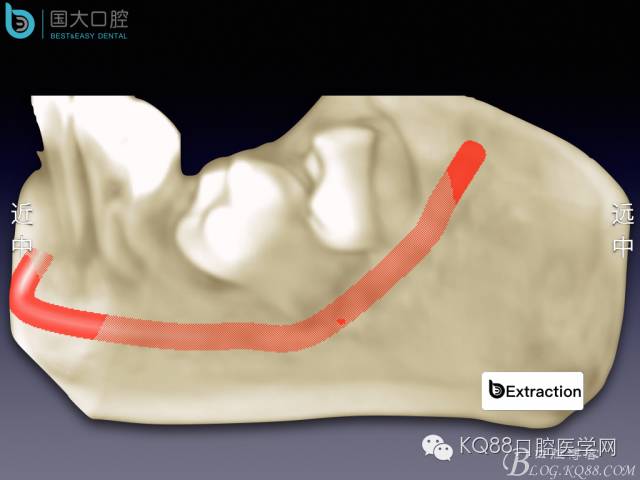

阻生牙的預(yù)防性拔除

- 牙齒拔除適應(yīng)證及第二磨牙遠中齲病